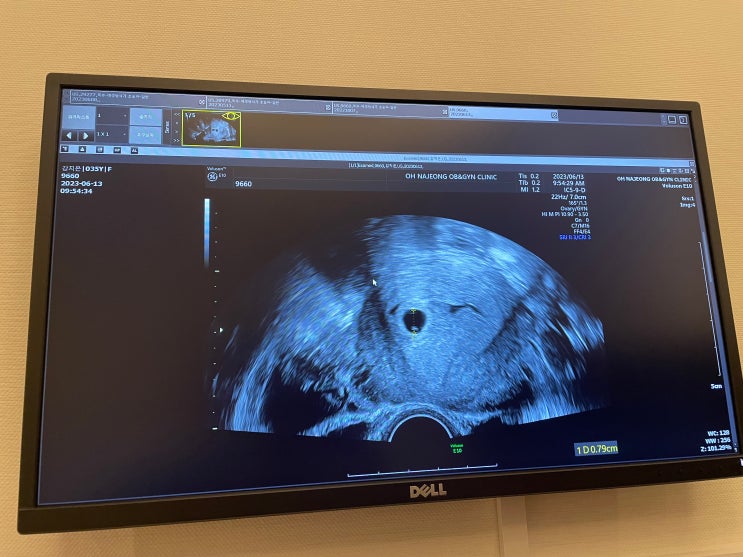

제주시에서 산부인과 선택하기! (오나정 산부인과, 제주대학교 병원)

이번 포스팅은 임신이 확정되면서 정기적으로 다닐 산부인과를 선택했던 후기를 간략하게 남겨본다. 병원 ...

임신 5주차, 임신 확정! 내 생애 첫 초음파, 난황과 아기집보고 보건소가서 임산부 배지 받던 날(feat. 태명과 베이비빌리, 그리고 임밍아웃)

'열달일기' 카테고리는 모두 남편인 내 시점에서 작성중이다. 임신 일기 포스팅은 대체로 임산부...